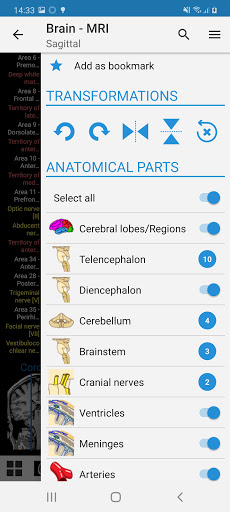

-You can now use Facebook or Google to sign in to the app.-The practice mode is now available in the lateral panel while viewing a module. (Structures names will be replaced with numbers and you can tap on it to display them)-Redesign and new nomenclature of coronary arteries for the module of the coronary angiogram and coronary CT. The anatomical terms are now more adapted to angiographic nomenclature and to cardiac imaging practice.-Fixed small bugs